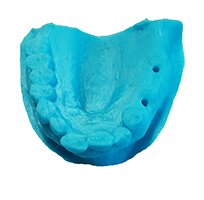

innovación dental

innovación dental